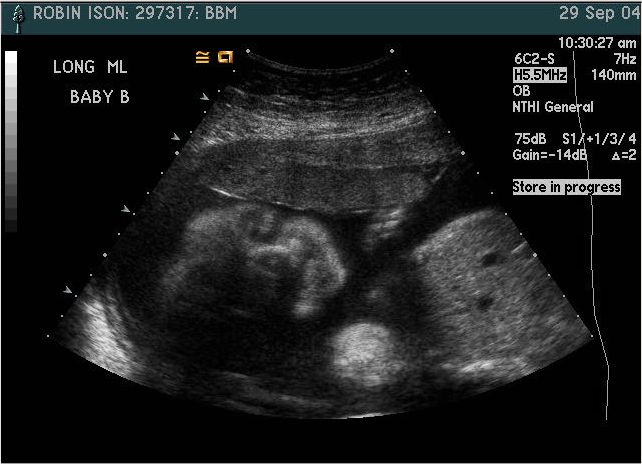

Baby B

Pictures from Ultrasound at 26 weeks.